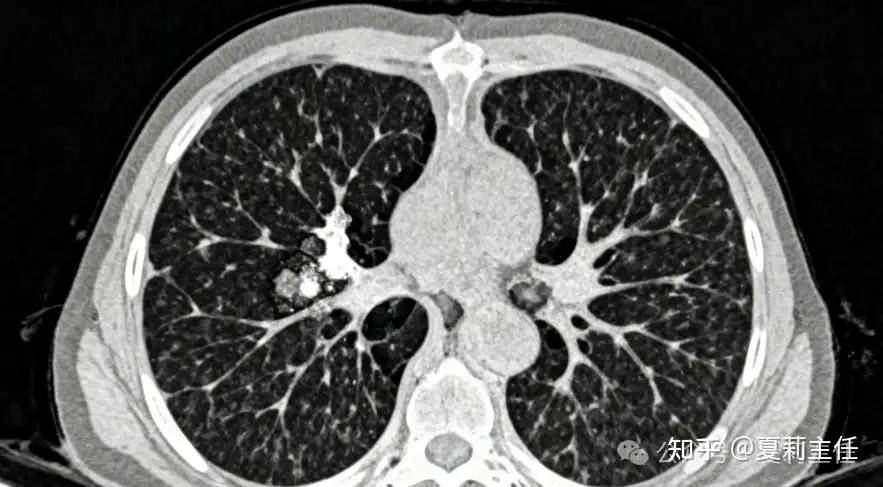

简单说,就是癌细胞只在原来肿瘤的 “老地盘” 附近卷土重来,没扩散到身体其他远处器官。比如肺部肿瘤切除后,在同侧胸腔、肺门淋巴结附近出现新病灶。

这种情况不用慌,如果没有转移到骨、脑、肝等远处,通过胸腔镜微创手术切除复发灶,或者用根治性放疗,多数患者仍有机会再次达到临床治愈,活得更久。